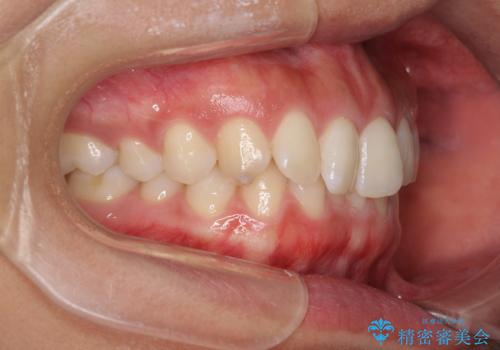

- 深い咬み合わせ(ディープバイト)と前歯のデコボコを気にして来院された患者様です。

インビザラインによる上下歯列の側方拡大と後方移動、IPR(歯と歯の間を削る)にるスペースの獲得により、デコボコとディープバイトを改善することとしました。

後方移動に際し、下顎の親知らずは2本とも抜歯することとしました。

1日22時間の装着時間をしっかり守ってくださったので、予定通り1年で治療を終えることができました。

ディープバイトによる食いしばり癖も解消され、患者様には大変満足していただきました。